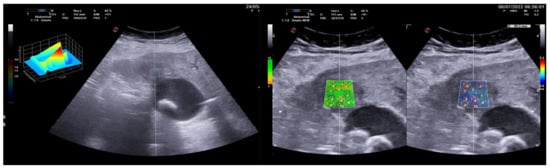

3.1. Group 1: Benign Focal Liver Lesions (Hemangiomas)